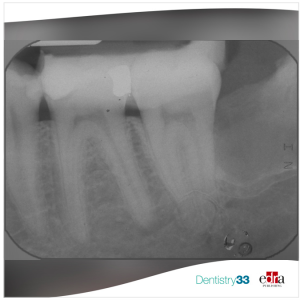

The research group selected 120 patients that according to inclusion criteria were divided into two groups (n = 60) to the type of restored tooth: Group 1, premolars and Group 2, molars. The patients of the molars and premolars group were further divided into 2 subgroups (n = 30) according to the presence or absence of a fiber post in the canal. Clinical and intraoral radiographic examinations were assessed during each recall (6 months and, 1, 2, and 3 years). Kaplan-Meier log-rank test and Cox regression analysis (Pp < 0.05) were applied.

After 3-y follow up, the authors reported a survival rate of ETT restored with or without fiber post on molars of 100%. Teeth with posts had no mechanical complications, whilst only premolars without posts showed 2 mechanical failures due to fracture of the abutment and root after two years. The Cox regression analysis showed that the presence of the post was not a significant factor for survival time. Furthermore, the group of Prof Ferrari found out that tooth type had an influence on survival time. Particularly, failure risk was greater for premolars.

From the results obtained in the present clinical study, after 3 years of observation the authors concluded that the use of the fiber post was not fundamental for the restoration of ETT with PPR, in fact no significant difference was recorded on both premolars and molars groups. In order to provide stronger evidence, longer-term data will be collected through further recalls.